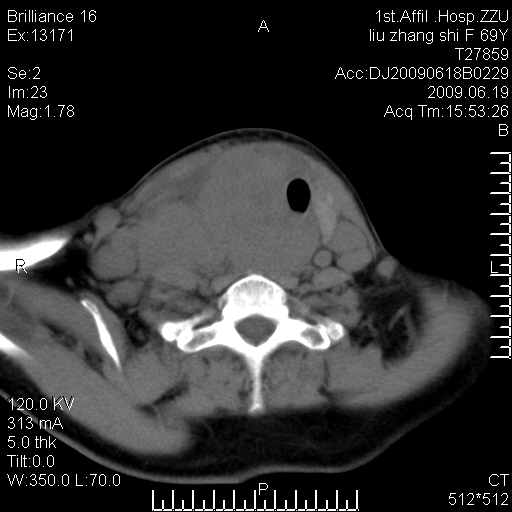

标题: CT26782:女,69岁,颈部占位,3天后公布病理结果。

【病理证实系列】女,69岁,颈部占位,有病理结果,3天后公布。(由于病例时间较久,临床资料不全,请网友见谅)本系列将有几百种常见、少见及罕见病例,均经病理证实。病例资料来自郑州大学第一附属医院。与网友共享,本人有空就发。

甲状腺癌并颈部淋巴结转移。感谢楼主的良苦用心,谢谢。

甲状腺癌并颈部淋巴结转移。

需与鼻咽癌鉴别!

支持甲状腺癌广泛侵及周围结构并颈部淋巴结转移。

鉴别:淋巴瘤、恶性神经源性病变、恶性纤维组织细胞瘤。

病理结果:颈部非霍奇金淋巴瘤。

右侧甲状腺确实有问题